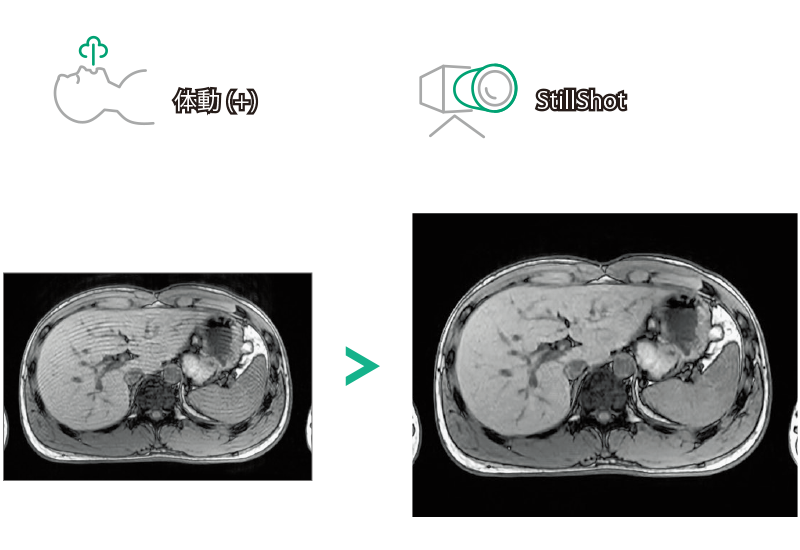

T1WI Dual Echo (Out) 息止め

T2*WI RADAR, 2:34

T2WI FatSat 呼吸同期併用RADAR, 2:16